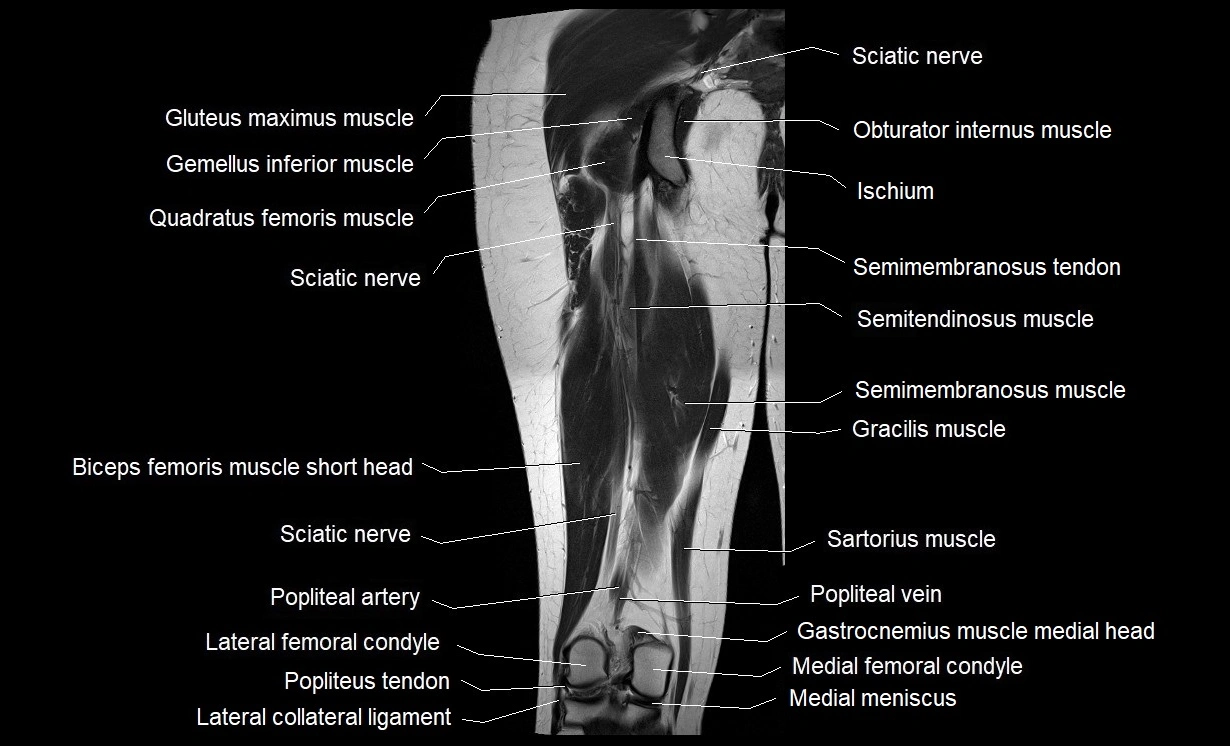

- Gluteus maximus muscle

- Gracilis muscle

- Inferior gemellus muscle

- Lateral collateral ligament

- Medial meniscus

- Popliteal artery

- Popliteal vein

- Popliteus muscle

- Popliteus tendon

- Quadratus femoris muscle

- Sartorius muscle

- Semimembranosus muscle

- Semimembranosus tendon (proximal)

- Semitendinosus muscle

- Tibial nerve